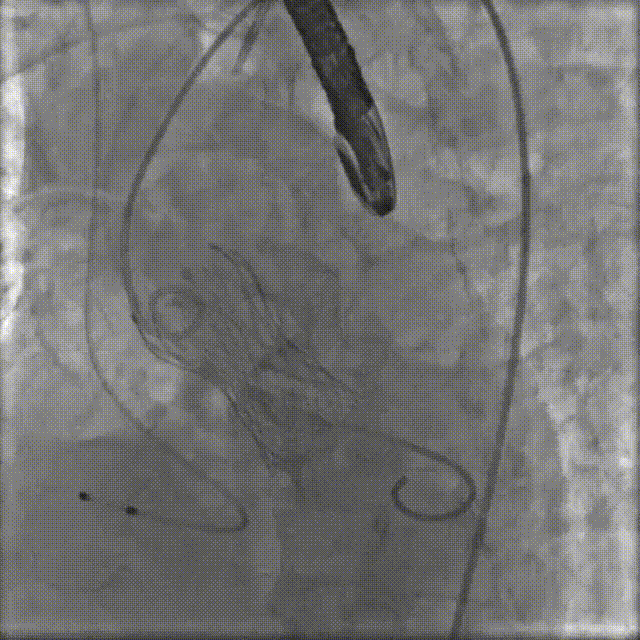

置入猪尾进行根部造影,造影可见根部钙化不均匀,冠脉灌注良好。

根部造影

20mm球囊预扩,无腰征,冠脉显影良好,无造影剂渗漏。

20mm球囊预扩

TaurusElite AV26瓣膜轻松过弓跨瓣,瓣膜初始定位瓣环0位,120bpm起搏下精准释放,释放到工作位后造影显示锚定充足,位置良好,冠脉未见遮挡,继续完成释放。

瓣膜初始定位

瓣膜释放过程

瓣膜释放后造影观察,根据影像判断反流较多,选择23mm球囊进行后扩。球囊后扩后反流量减少,瓣膜形态佳。

瓣膜脱钩

工球囊后扩

释放后多体位观察造影,提示瓣膜位置良好,展开良好,双侧冠脉未见遮挡,微量瓣周漏。

最终造影